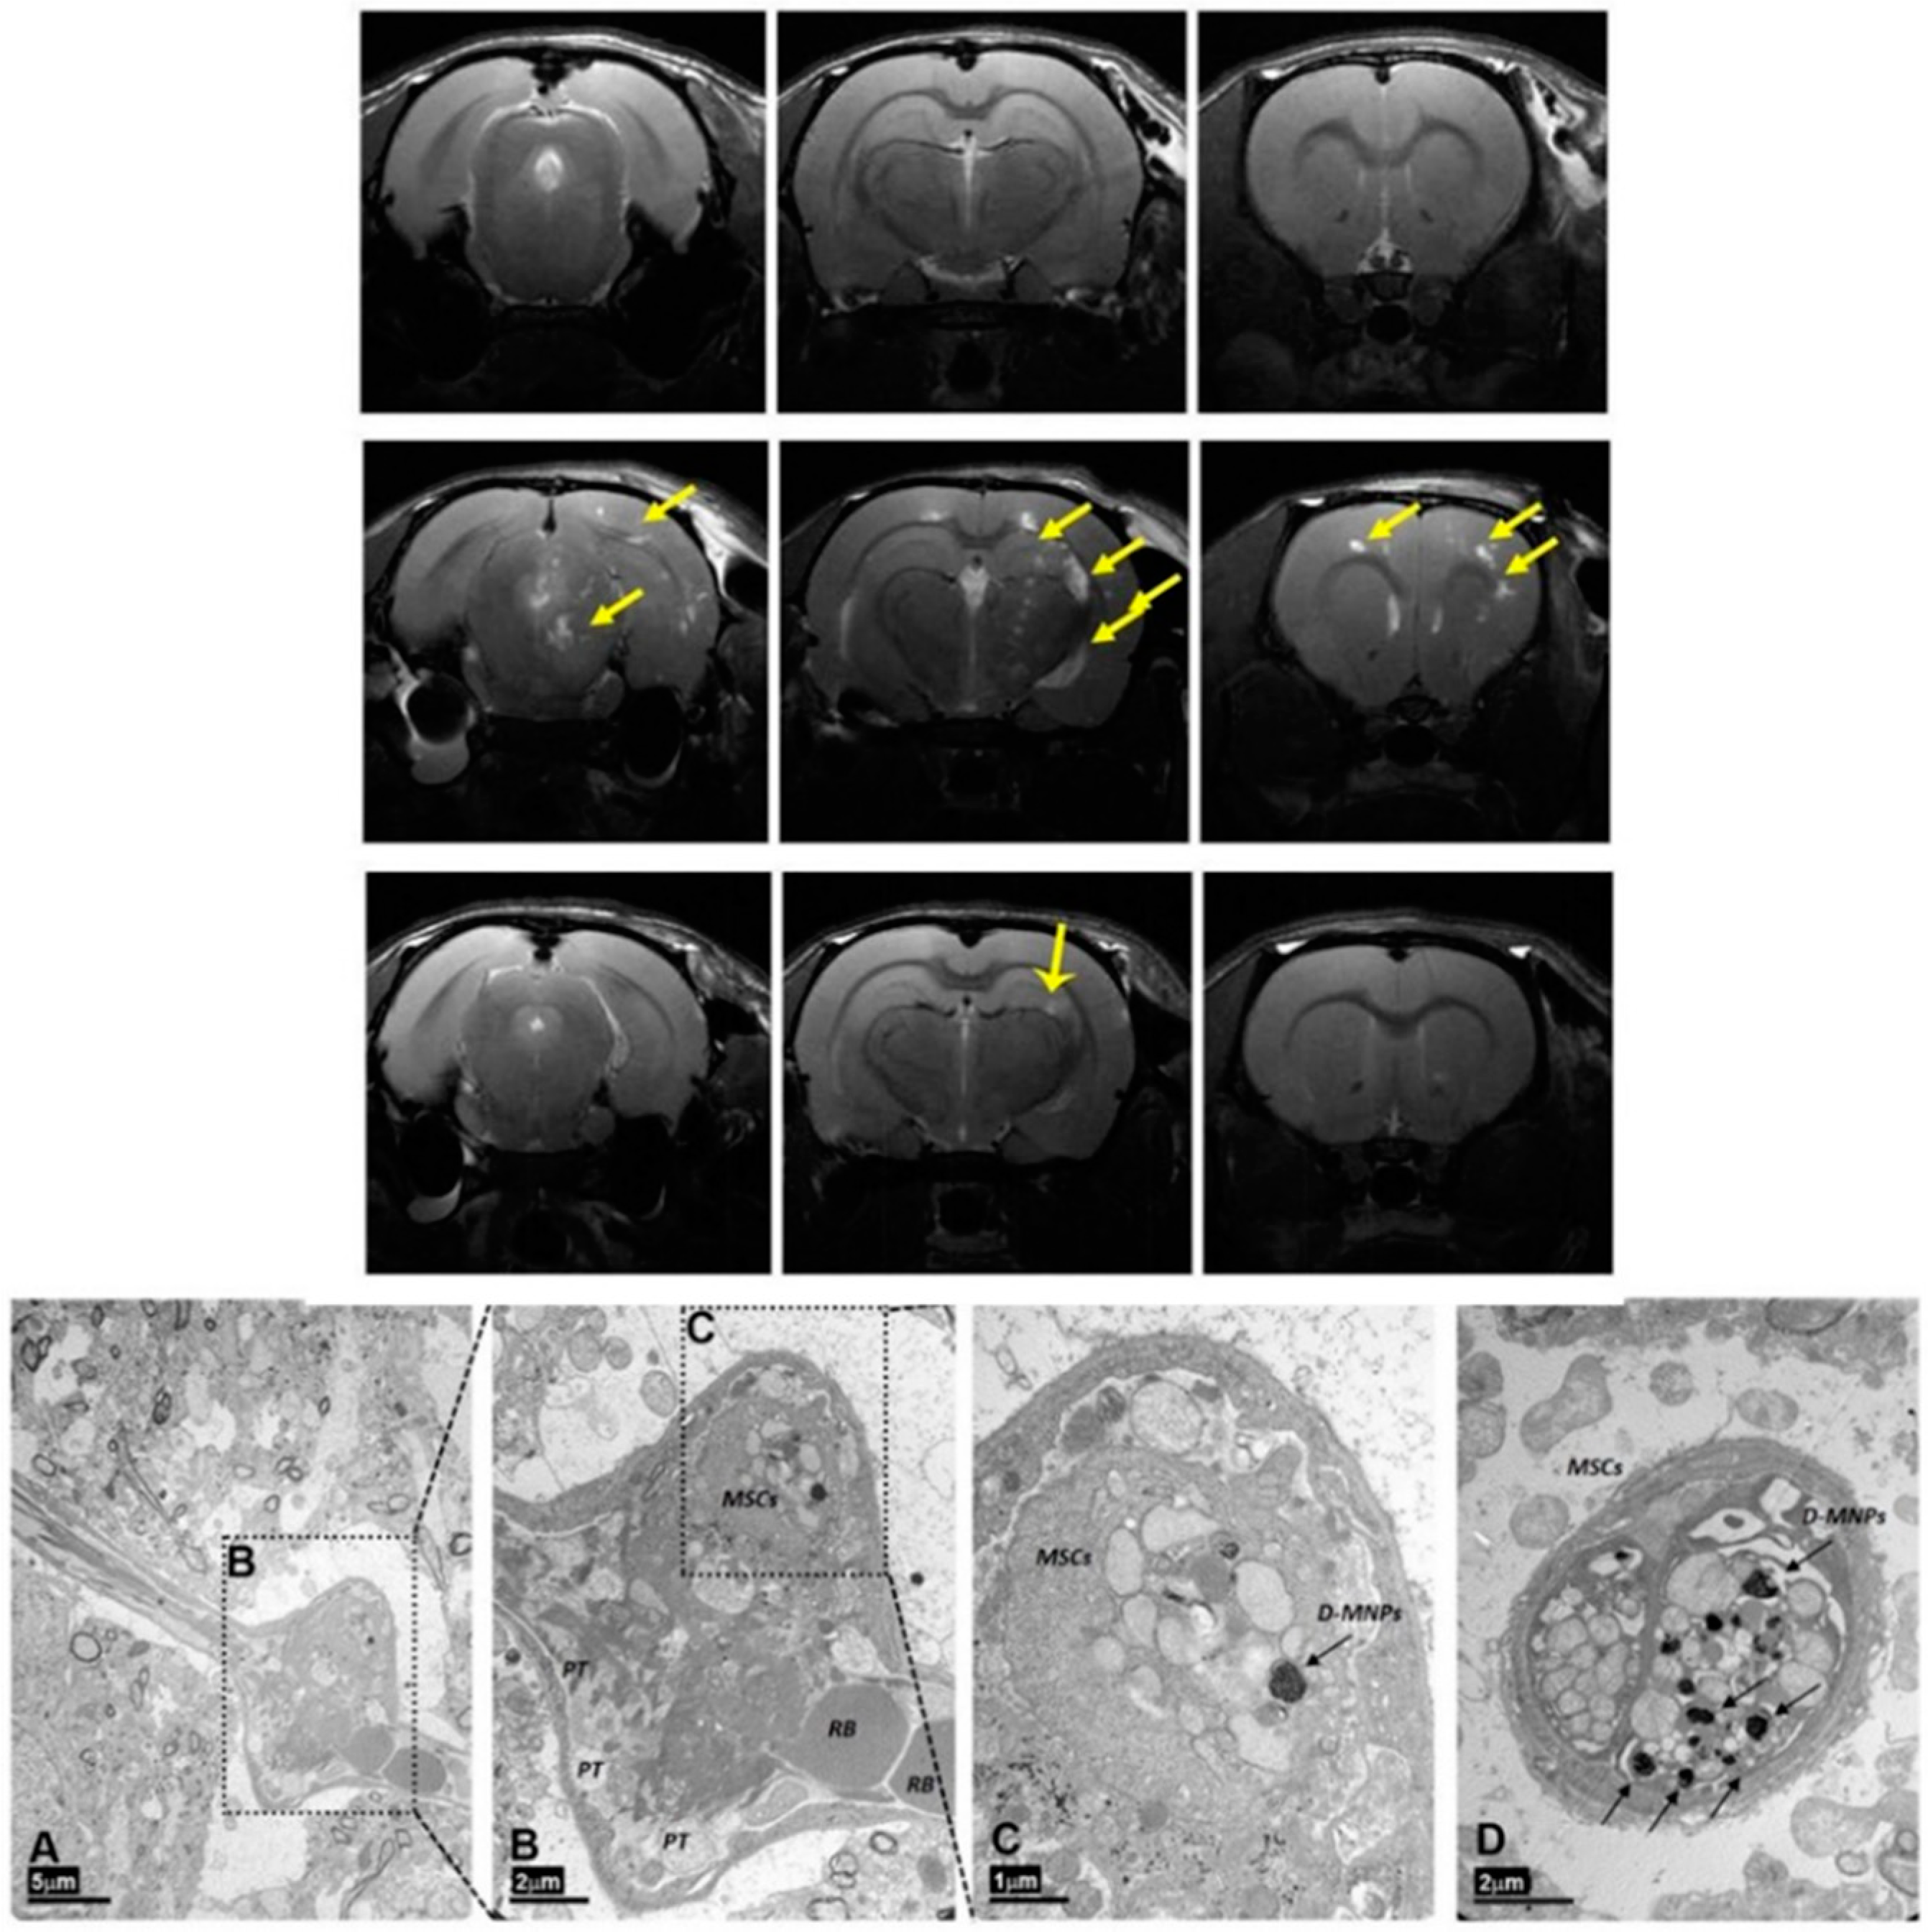

5.2. MNPs for MRI Cell Tracking in Stroke

- Argibay, B.; Trekker, J.; Himmelreich, U.; Beiras, A.; Topete, A.; Taboada, P.; Pérez-Mato, M.; Vieites-Prado, A.; Iglesias-Rey, R.; Rivas, J.; et al. Intraarterial route increases the risk of cerebral lesions after mesenchymal cell administration in animal model of ischemia. Sci. Rep. 2017, 7, 40758. [Google Scholar] [CrossRef]